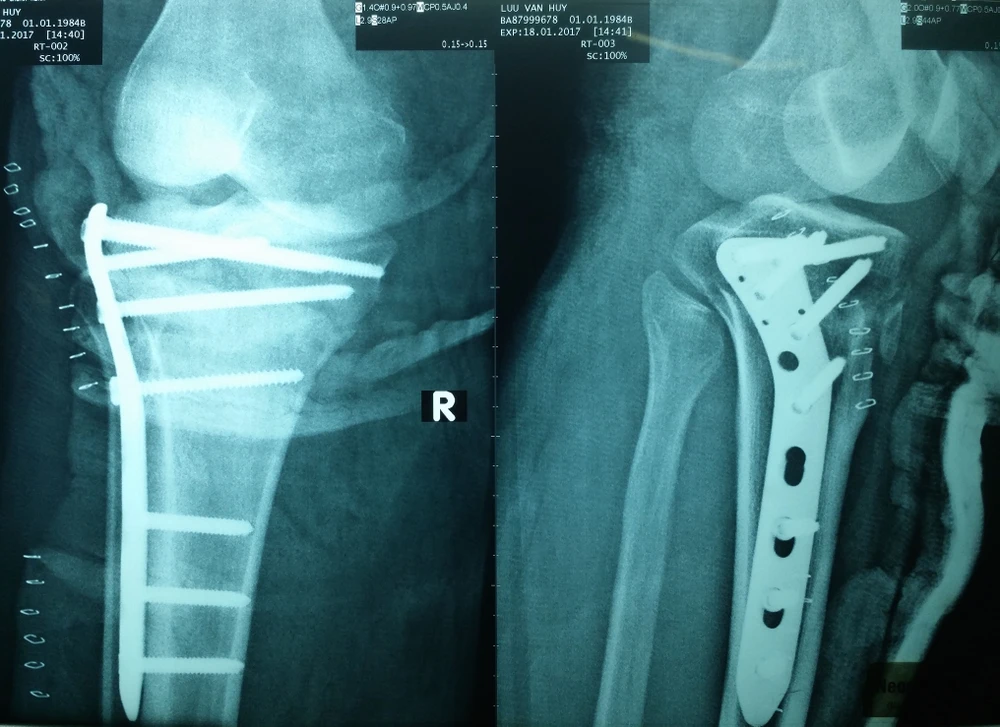

Với sự phối hợp của các BS Võ Hòa Khánh, Trương Viết Thông và  Đinh Ngọc Minh, ê kíp phẫu thuật tiến hành kết hợp xương bằng đường mổ ít xâm lấn dưới sự hỗ trợ của màn tăng sáng (CARM). Sau bốn tiếng phẫu thuật, các BS chẳng những phục hồi xương cho bệnh nhân mà còn phục hồi lưu thông mạch máu trong một lần mổ duy nhất.

Bệnh nhân được phẫu thuật kết hợp xương bằng đường mổ ít xâm lấn dưới hỗ trợ của màn tăng sáng. Ảnh: VIẾT THÔNG